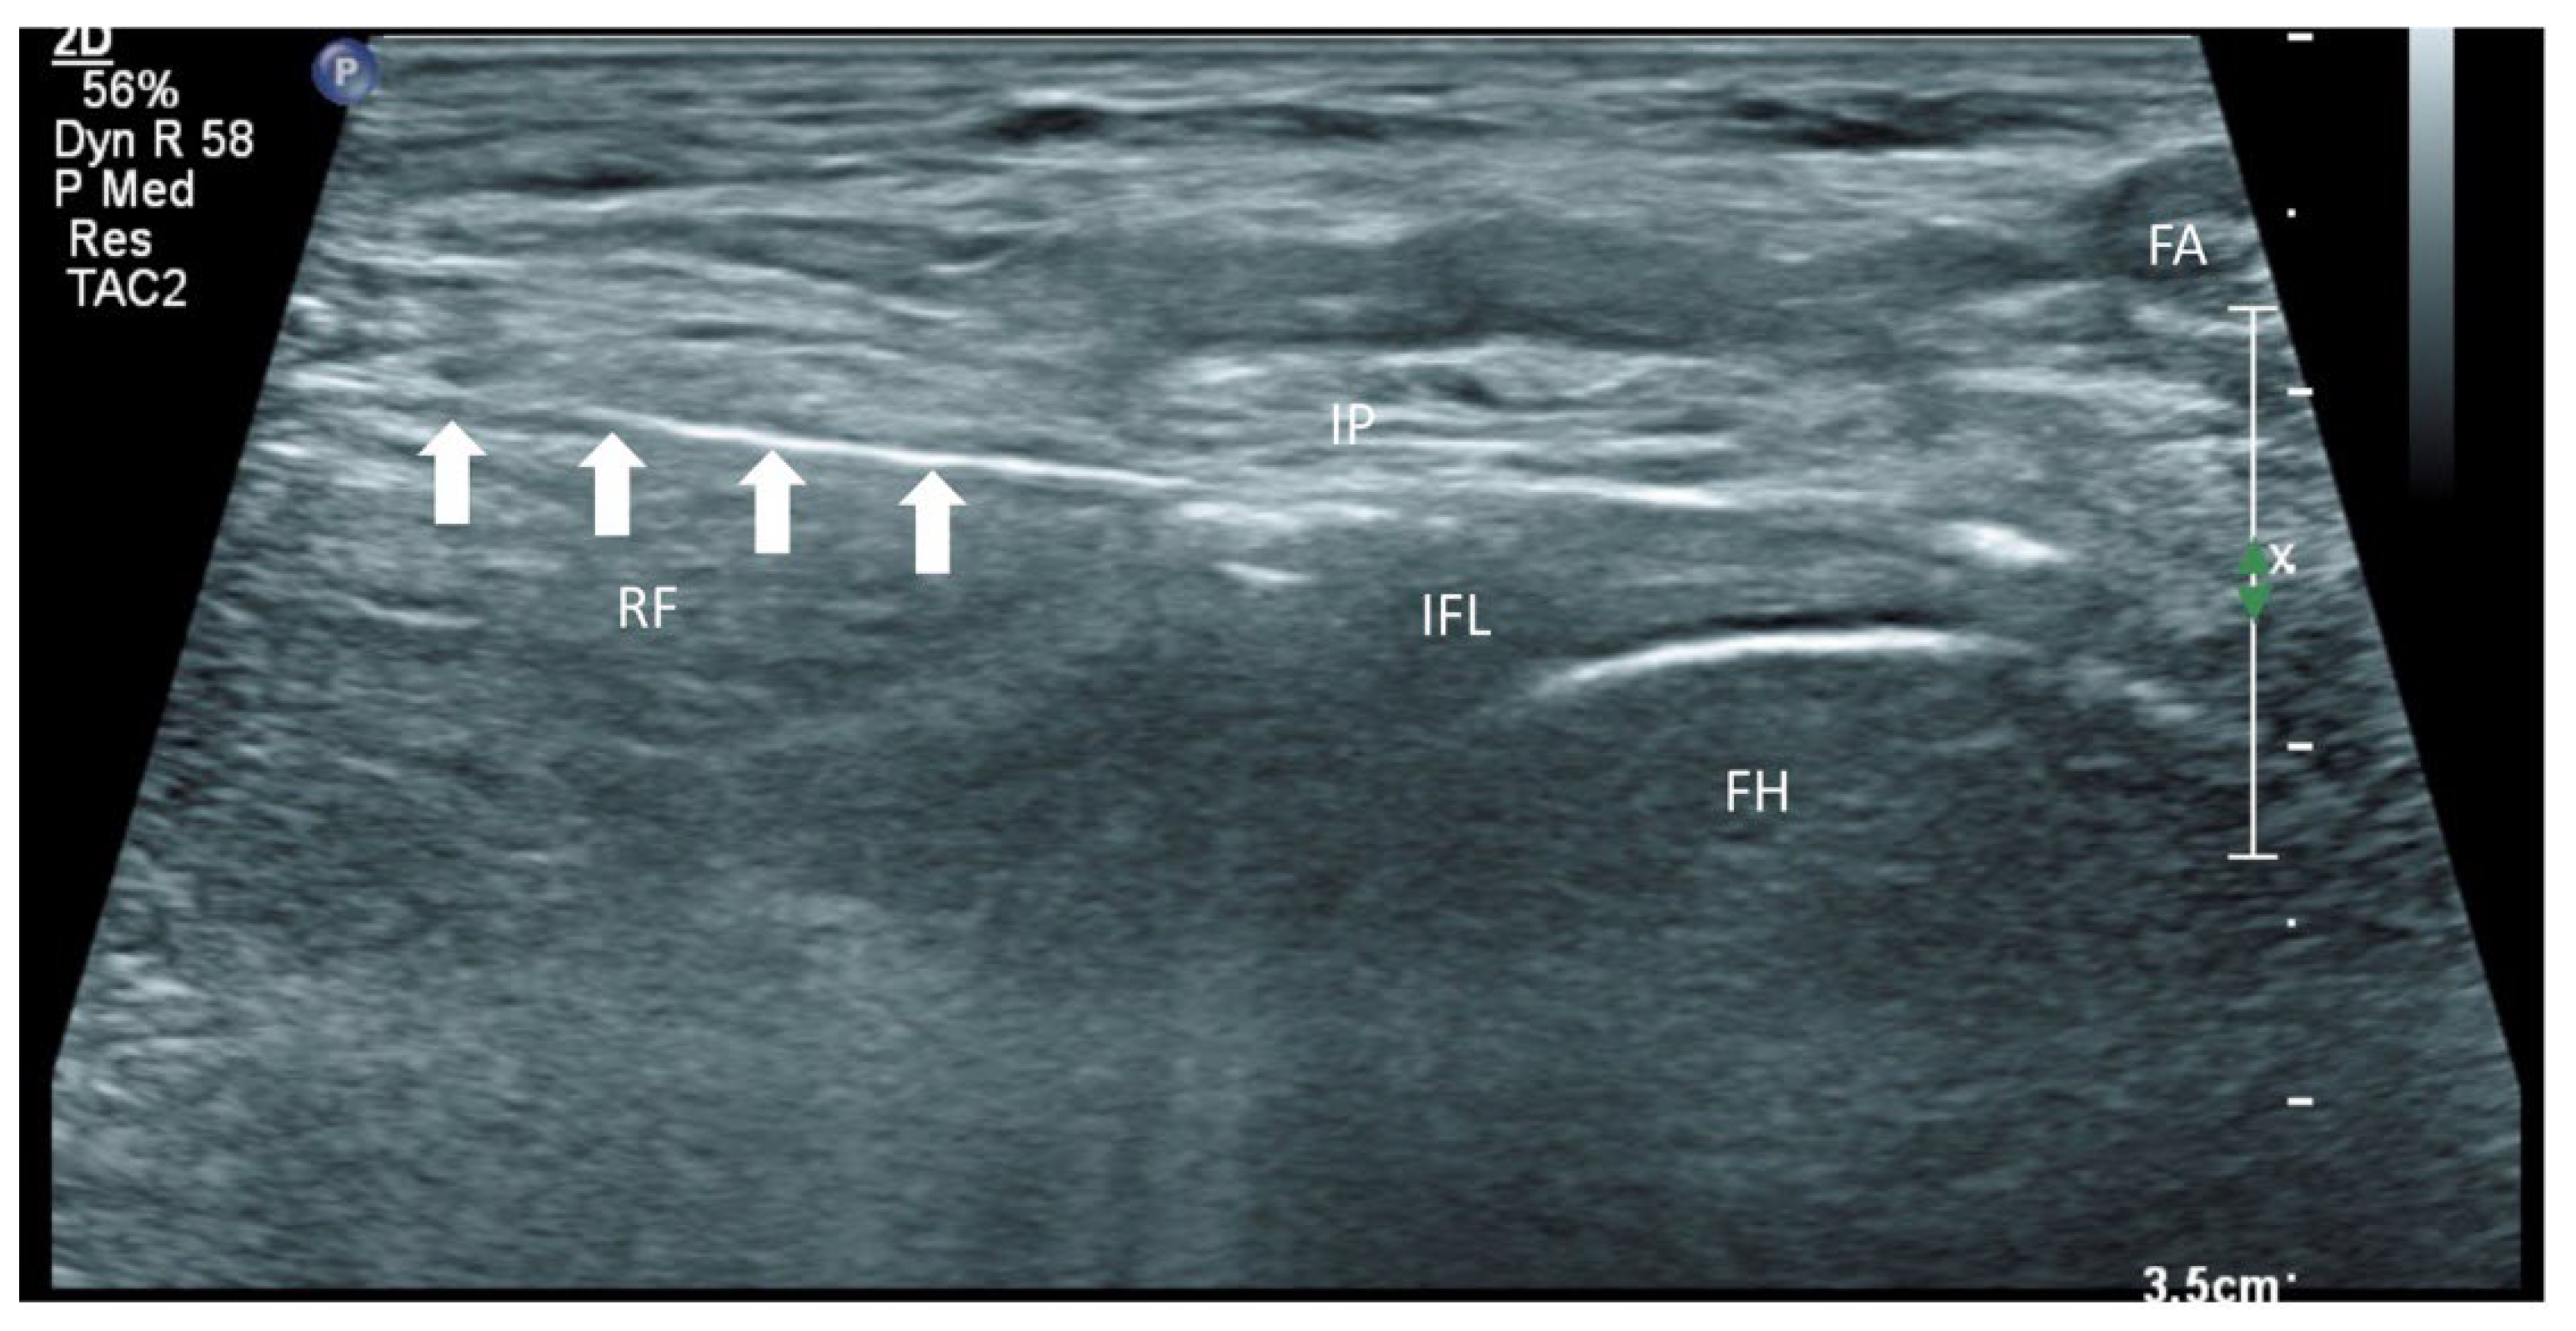

Figure 2. A schematic diagram to show how the linear probe is placed to align the AIIS and IPE. Reproduced with permission from Dr Maria Fernanda Rojas Gomez (Bucaramanga, Colombia). Green dot: transducer mark.

In addition to the classical PENG injection, our modified approach highlighted the addition of pericapsular infiltration in the iliopsoas plane to cover the low articular branch of the femoral nerve and a sagittal approach to target the ONAB. The algorithm was still used to perform diagnostic blocks, followed by alcohol neurolysis 10 min later for those with a positive diagnostic block in the same setting under real-time ultrasound guidance (Philips Affiniti 70, 5–12 MHz linear probe or 1–5 Hz curved probe depending on the depth of the target). In the modified approach, the procedure consisted of 3 needle insertions with the use of 22-gauge 10 cm Quincke needles. The first needle for the high femoral nerve articular branches (high FNAB branches) and AON was inserted in the same way as the PENG approach between the anterior inferior iliac spine (AIIS) and the iliopubic eminence (IPE) deep to the psoas tendon (Figure 2 and Figure 3). A second needle for the low branches of FNAB was inserted in-plane from lateral to medial and advanced through the sartorius, rectus femoris and iliopsoas muscles. The final needle position was in the plane superficial to the iliofemoral ligament medial to the rectus femoris tendon over the femoral head (Figure 4 and Figure 5). The third injection for the obturator nerve articular branches was used to target the caudal aspect of the inferomedial acetabulum (IMA) by scanning in a sagittal plane with a caudal-to-cephalad needle trajectory. The precise localization of the caudal aspect of the IMA could be first approached via the ordinary way (an oblique scan) as described in our first case series [5]. The probe was slowly rotated obliquely until the acetabulum, femoral head, and neck were aligned in the same plane, with the superomedial acetabulum coming into view. The probe was then slid caudally with the end point being the presence of the acetabulum without the femoral head. This referred to the location of the inferomedial acetabulum. The probe was then adjusted until the IMA was in the middle of the image, followed by rotating the probe by approximately 60 degrees (Figure 6). In this scan, the pectineus, the caudal aspect of the IMA and, occasionally, the obturator externus were seen. The ONAB could be visualized in the wedge of the subpectineal space directly adjacent to the IMA. Before any needle insertion, the probe was tilted slightly medially towards the obturator foramen to look for the acetabular/posterior branch of the obturator vessels which are usually deeper than the ONAB. The needle was then inserted from caudal to cephalad in-plane until the needle tip reached the wedge space consisting of the ONAB (Figure 7). In case the wedge space could not be clearly visualized, the needle tip would then be advanced until touching the caudal bony surface of the IMA directly underneath the pectineus. Then, 0.5–1% ropivacaine (4, 3 and 2 mL, respectively) was injected into the above three landmarks. The needles were left in situ during the diagnostic test while their positions were reconfirmed by ultrasound before 100% alcohol was injected into the above targets with volumes in a 1:1 ratio between alcohol and local anaesthetics. A decrease of ≥50% in composite pain score on hip flexion at 45 degrees 10 min after the blocks signified a positive diagnostic block. As a post-neurolysis routine manner, stylets were reinserted before needle withdrawal.